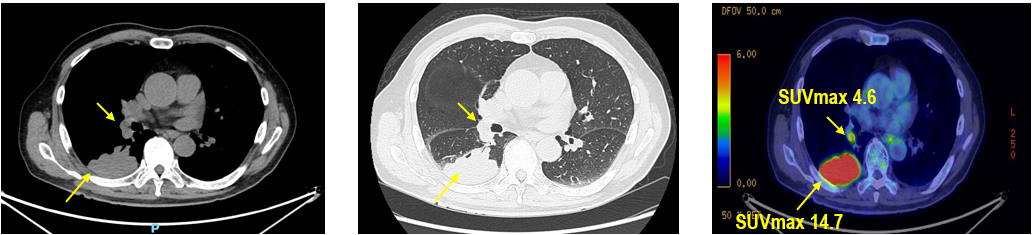

PET-CT(2023年9月):右下肺叶发现6.9×6.7×6.6cm的FDG高摄取肿块,伴右侧第7、8肋骨侵犯可疑,右肺门淋巴结肿大,双肺上叶多发结节,考虑腺癌谱系疾病。

CT及PET-CT随访(2023年11月、2024年1月):评估新辅助治疗效果,右下肺叶肿块缩小,右肺门淋巴结代谢活性消失,右肺上叶结节稳定但代谢活性降低,左肺上叶及双侧磨玻璃样病变稳定。